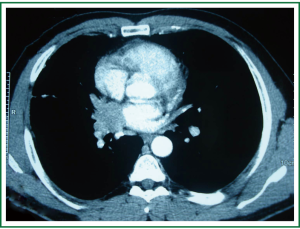

In physical examination, vital signs were normal, general and respiratory examination was unremarkable. Apart from a high fasting glucose level 177 mg/dL, eritrocyte sedimentation rate 48 mm/hr, liver function tests (AST: 73 IU/L, ALT: 92 IU/L), rutine laboratory analysis were normal. Respiratory function tests and oxygenation in room air were normal. The chest radiograph revealed prominence of right hilum and infiltration in the anterior segment of right upper lobe. A computed tomography scan revealed a 4 cm mass lesion in the right hilum and multiple mediastinal conglomerated lymph nodes (Figure 1). A PET/CT scan (Figure 2) demonstrated significantly increased activity (SUVmax: 9.74) at the right hilar mass lesion and right lower paratracheal (SUVmax: 3.57), subcarinal (SUVmax: 4.83), prevascular (SUVmax: 5.76) lymph nodes. Fiberoptic bronchoscopy showed mucosal distortion of right upper lobe. Pathologic examination of the mucosal biopsy revealed inflammation. Endobronchial ultrasound guided transbronchial needle biopsy from the hilar mass, right lower paratracheal and subcarinal lymph nodes revealed CD-45 positive normal lymphoid cells without any evidence of malignancy (Figure 3). Cervical mediastinoscopic biopsies of right lower paratracheal and subcarinal lymph nodes were undiagnostic. Diagnostic thoracotomy confirmed the diagnosis fibrosing mediastinitis. Hilar mass was a conglomerated lymph node showing dense hyalinized fibrous tissue with chronic inflammation (Figure 4). We administered 6 months of systemic corticosteroid and antituberculous therapy (Isoniazid, rifampicin, pirazinamid, ethambutol for two months and isoniazid, rifampicin for four months). A thorax tomography performed after discontinuation of therapy revealed similar findings with the postoperative thorax tomography.

In computed tomography, fibrosing mediastinitis is strongly suggested by the obliteration of fat planes of the mediastinum and the presence of discrete masses and/or extensive calcified paratracheal, hilar and subcarinal lymphadenopathy causing circumferential encasement of the mediastinal structures (4,6). Sometimes it is difficult to distinguish a discrete mass from a malignant process despite enhanced imaging modalities. It can mimic a bronchogenic carcinoma in countries outside endemic fungal infection areas (5).

In the endemic areas, the diagnosis is usually based on typical clinical and radiological findings (1). Mediastinoscopy or thoracotomy may be necessary to exclude malignancy and to confirm diagnosis (4). But in the presence of atypical features invasive diagnostic procedures are needed (7). It is usually difficult to make an accurate histopathological diagnosis using minimally invasive methods. Consequently many patients with fibrosing mediastinitis undergo surgical biopsy of the mediastinum to confirm the diagnosis and rule out a neoplasm. In this patient, there was a non-calcified right hilar mass lesion on CT scan. On PET/CT there was a high uptake of fluorodeoxyglucose both on the right hilar mass lesion and mediastinal lymph nodes. Endobronchial ultrasound guided mediastinal lymph node biopsies and mediastinoscopic biopsies were undiagnostic that the patient was sent to thoracotomy.